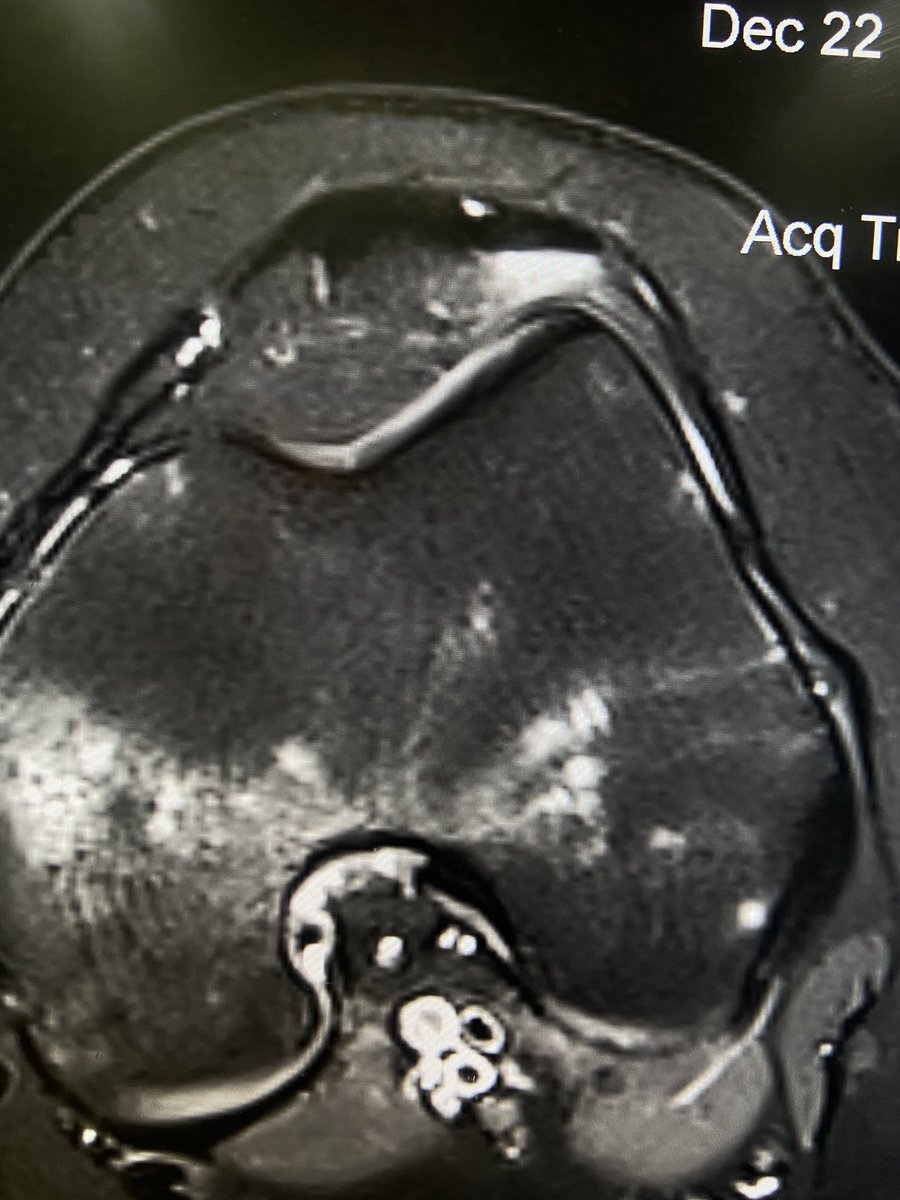

@mskteachingroom @mskradiologyuk @SidThakerMSK @jacja_ @veronica_giotas @PrimeFellowship Migrations of Ca tendinopathy

Spot Diagnosis?

The scapular ‘Y’ view is excellent for detection of coracoid fracture at the shoulder! [in this case not seen on AP internal / external rotation views]